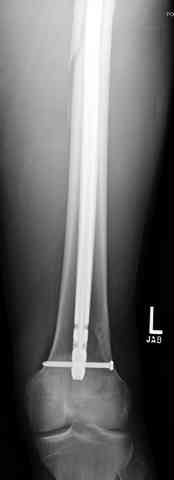

Здесь представлены несколько случаев лечения огнестрельного перелома

1 Проксимальный перелом бедра, антеградный гвоздь

Для фиксации огнестрельных переломов бедра и длинных костей предпочтение отдаем интрамедуллярному методу фиксации, о котором еще в 1993 году написали Bergman M. Tornetta P. Kerina M. Sandhu H. Simon G. Deysine G. Journal of Trauma. [JC:kaf] 34(6):783-5